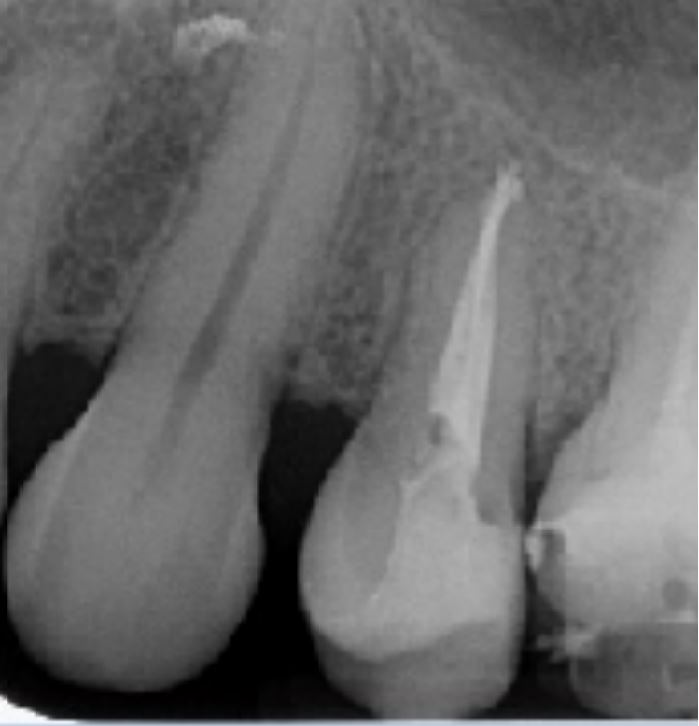

Radio post-opératoire

Obturation Gutta et Ciment Zinc Eugénol

Thermocompactage

Composite de restauration 2 faces occluso-distal